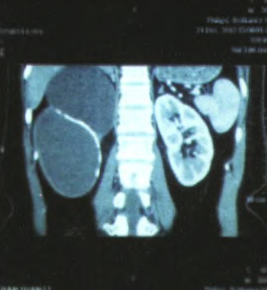

B超检查提示:右肾上极可见一约113mm*88mm囊性结构。 双肾增强CT检查提示:增强扫描提示右肾区囊性低密度影,囊壁钙化,未见明显强化,大小同平扫,周围可见少许强化之肾实质

予完善相关术前准备,查无明显手术治疗。予行腹腔镜下肾囊肿去顶减压术。 术后病理提示:纤维组织囊壁伴透明样变性,囊肿内容物系坏死组织。 术后患者出现持续发热,体温最高达39.3℃,行双肾CT平扫提示肾上极囊肿大小与穿刺抽液前大小相同,无明显缩小,经重新审视病历考虑该患者可能系肾囊肿合并肾上极巨大。肾盏憩室,给予行双肾CT平扫+逆行造影后双肾平扫提示:右肾钙化囊肿减压术后改变,囊肿缩小,张力明显减小,但囊肿壁有卷曲,肾上极较大囊内可见较多造影剂。经科室讨论明确诊断,考虑发热系肾中部钙化囊肿内坏死物质吸收所致,而肾上极“囊肿”为肾盏憩室,遂行右。肾探查术,术中见残余肾组织大小已不足正常肾脏1/6,残余肾组织被囊肿及肾盏憩室挤压变薄,考虑如保留肾脏可能术后发生较多并发症遂行肾切除术,术后标本可见肾盏憩室与肾盂相通,右肾囊肿囊壁钙化并较硬,厚度约1cm。